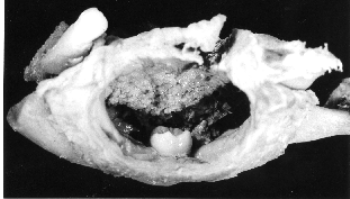

- Mandible with a follicular odontome

- Mandible with a follicular odontome The preparation is a portion of the left half of an adult mandible, showing a follicular odontome, a type of benign tumour. Posterior to the second premolar tooth the body and ramus of the mandible is expanded to form an unilocular cyst around the crown of the unerupted 3rd molar tooth. The wall of the cyst is fibrous and at least 2 mm. thick and the cavity is lined with irregular fibrinous inflammatory deposit.